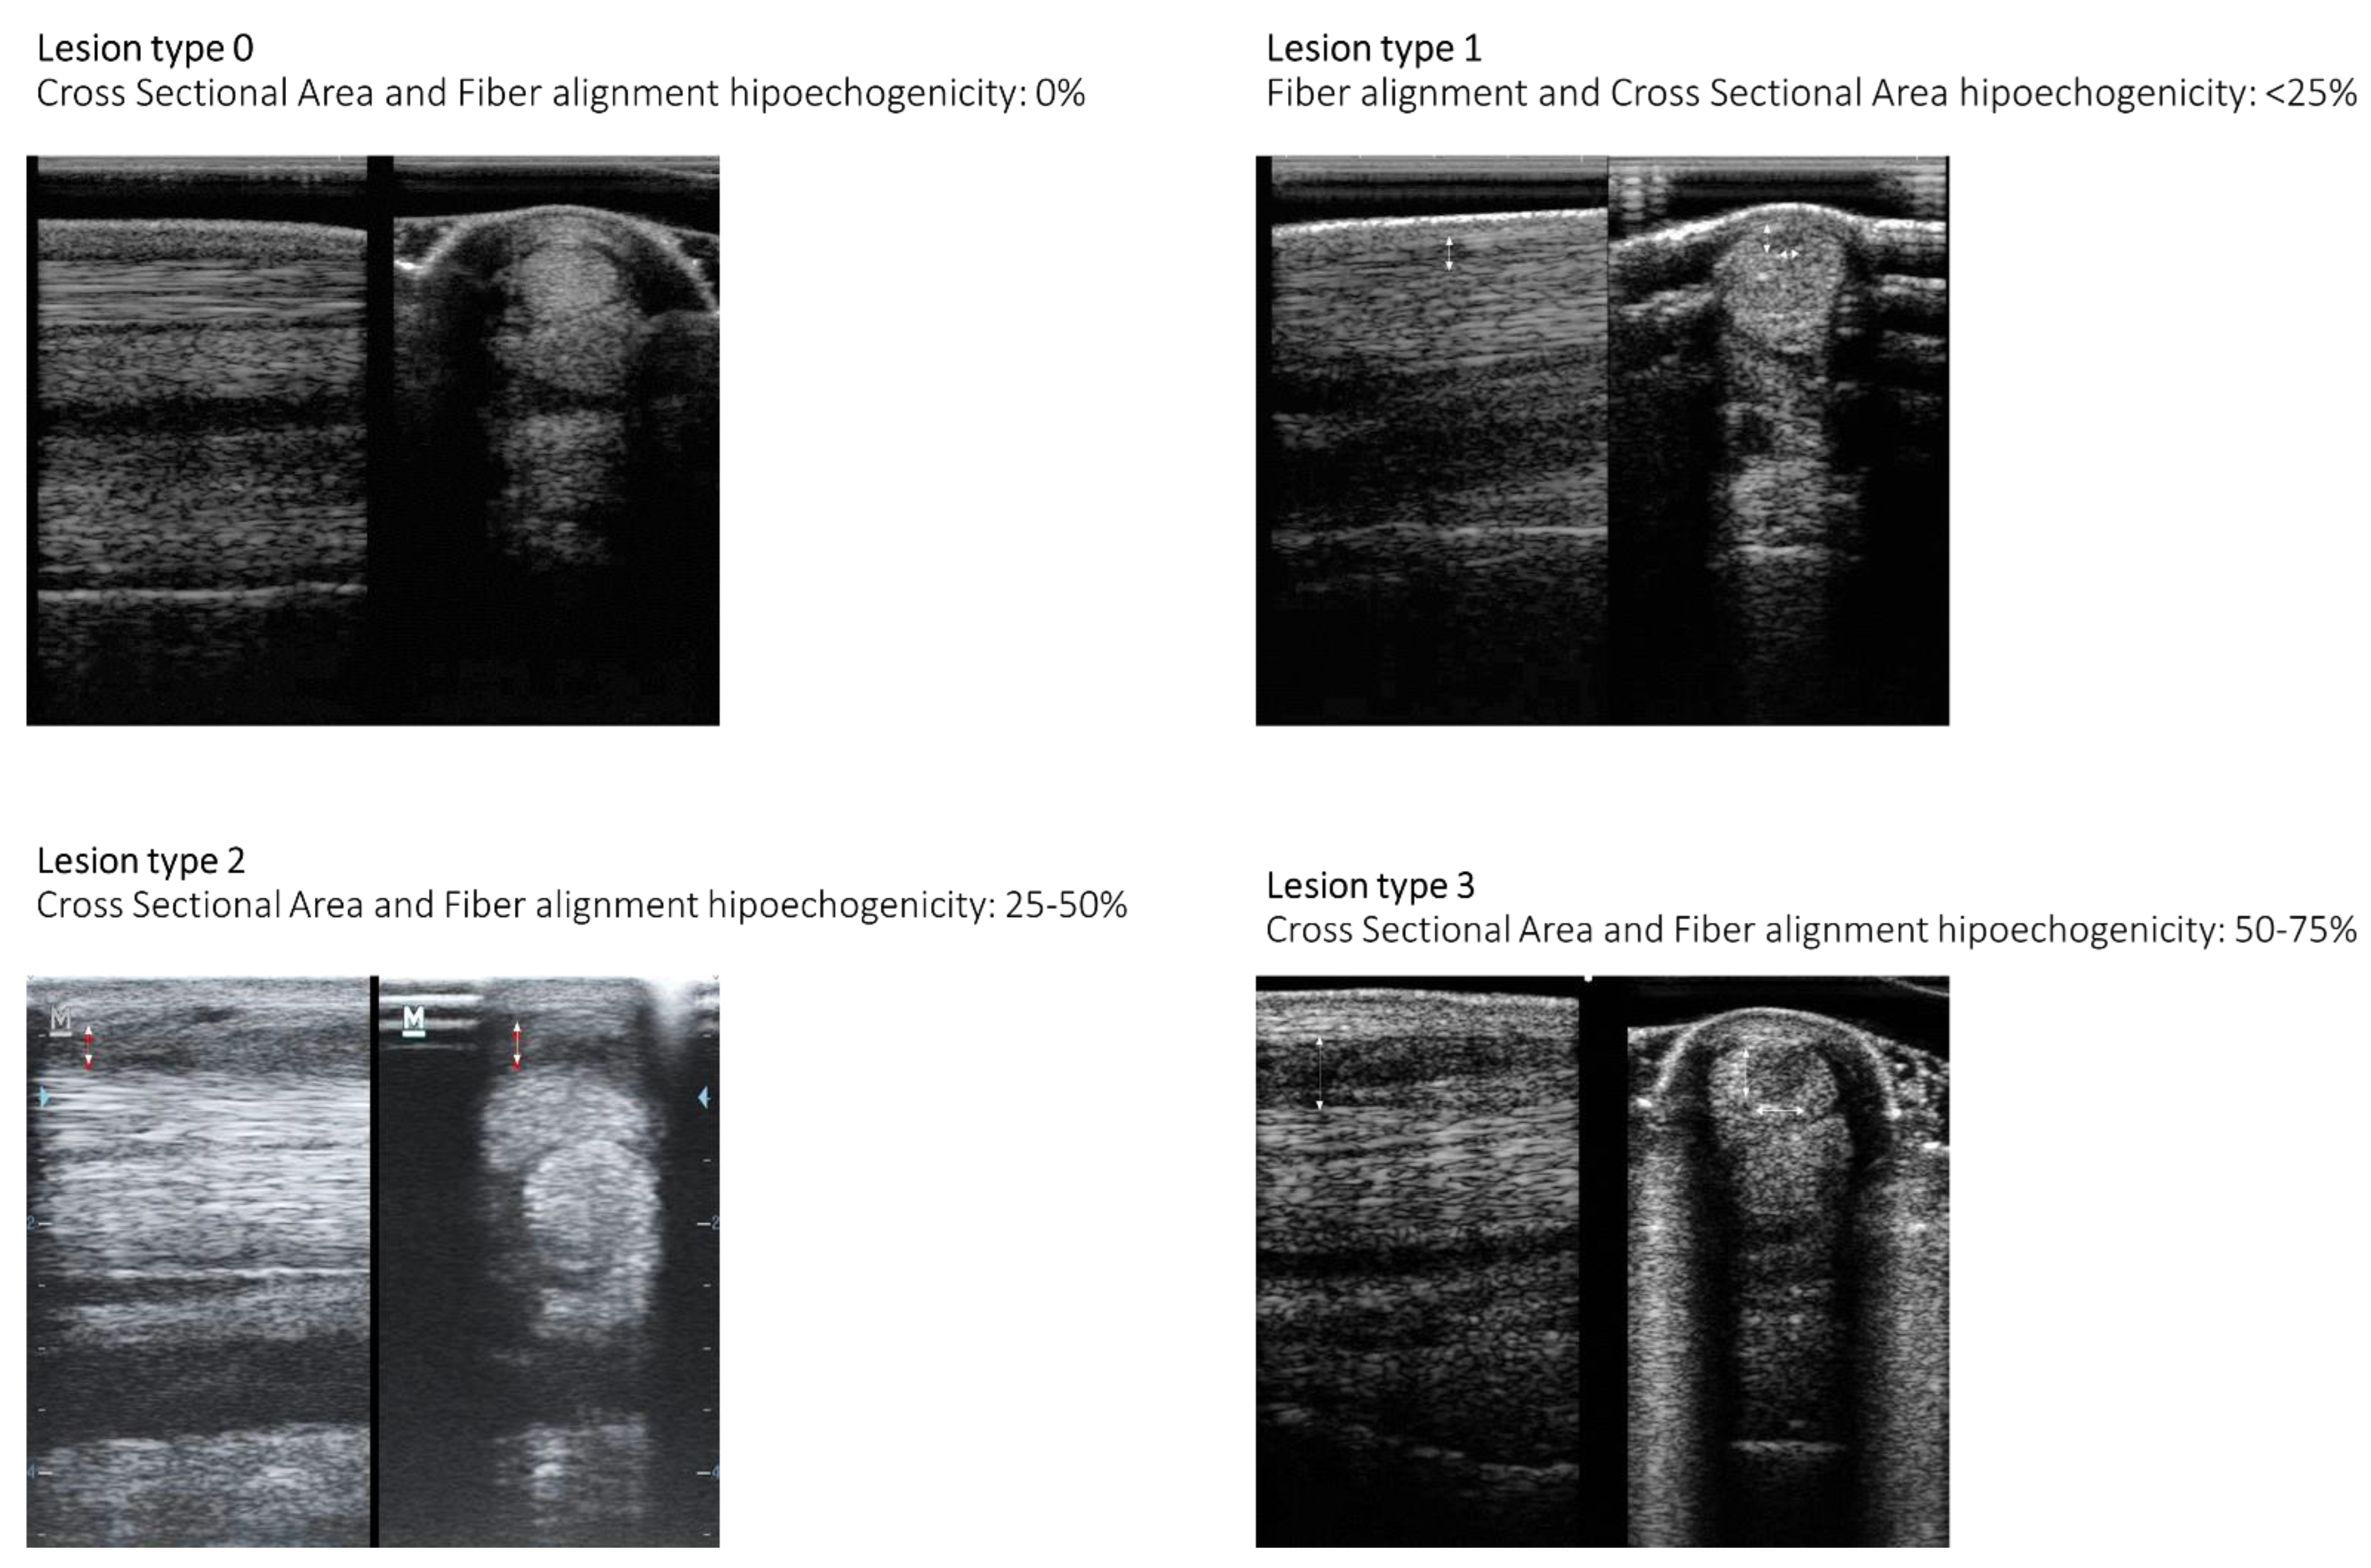

| Patient ID | Day | Structure | Location | Cross-Sectional Area | Longitudinal Fiber Pattern (%) | Assessment Outcome |

|---|---|---|---|---|---|---|

| 1 | 1 | SDFT | 1A-1B | 1 | 1 | |

| DDFT | 1A-1B | 1 | 1 | |||

| 15 | SDFT | 1A-1B | 1 | 1 | ||

| 30 | SDFT | 1A-1B | 0 | 0 | Full function | |

| DDFT | 1A-1B | 0 | 0 | |||

| 2 | 1 | SDFT | 1A-1B | 1 | 1 | |

| 3 | 1 | SDFT | 1A-1B | 1 | 1 | |

| 4 | 1 | SDFT | 1A-1B | 2 | 2 | |

| 15 | SDFT | 1A-1B | 2 | 2 | ||

| 5 | 1 | LB SL | 3A-3B | 2 | 2 | |

| 15 | LB SL | 3A-3B | 2 | 2 | ||

| 30 | LB SL | 3A-3B | 0 | 0 | Full function | |

| 6 | 1 | SDFT | 2A-2B | 2 | 2 | |

| DDFT | 2A-2B | 2 | 2 | |||

| SL | 2A-2B | 2 | 2 | |||

| 15 | SDFT | 2A-2B | 1 | 1 | ||

| DDFT | 2A-2B | 1 | 1 | |||

| 30 | SDFT | 2A-2B | 1 | 1 | Unacceptable function. Only at day 90. | |

| LS | 2A-2B | 1 | 1 | |||

| 7 | 1 | SDFT | 2A-2B | 3 | 3 | |

| 15 | SDFT | 2A-2B | 3 | 3 | ||

| 30 | SDFT | 2A-2B | 2 | 2 | Unacceptable function. | |

| 8 | 1 | SDFT | 2A-2B | 2 | 3 | |

| 15 | SDFT | 2A-2B | 2 | 2 | ||

| 30 | SDFT | 2A-2B | 0 | 0 | Full function | |

| 9 | 1 | SDFT | 2A-2B | 2 | 1 | |

| 10 | 1 | SDFT | 1A-1B | 3 | 3 | |

| 11 | 1 | SDFT | 1A-1B | 2 | 2 | |

| 12 | 1 | SDFT | 2A-2B | 1 | 1 | |

| 13 | 1 | SL | 1A-1B | 2 | 2 | |

| 15 | SL | 1A-1B | 1 | 1 | ||

| 30 | SL | 1A-1B | 0 | 0 | Full function | |

| 14 | 1 | SDFT | 2A-2B | 1 | 1 | |

| 15 | 1 | SDFT | 2A-2B | 2 | 2 | |

| 16 | 1 | SDFT | 2A-2B | 2 | 2 | |

| 30 | SDFT | 2A-2B | 0 | 0 | Full function |